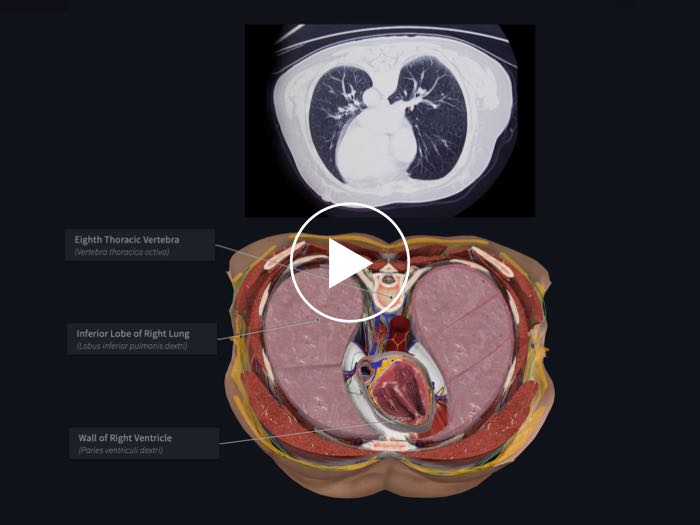

Cross-Sections

Take transverse cross-sections through any structure to learn about it in context and compare with MRIs

Radiology

Explore a suite of radiology images and correlate their structures to the 3D model